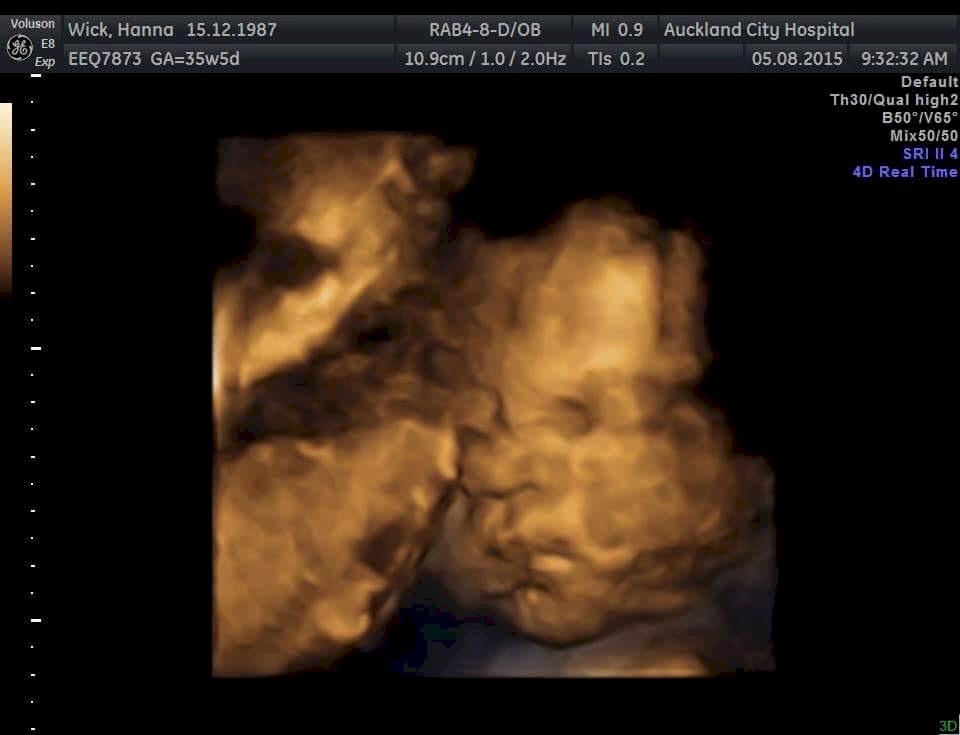

Update from Hanna and Scott: Mid transfusion check up today went well she looking good.. (blood transfusions have helped her a lot) 35 weeks tomorrow ekkk even came away with a 4D scan altho she didn't look impressed about it lol... also now have date for induction... 17th august so we are having her in 2 and a half weeks time !!!